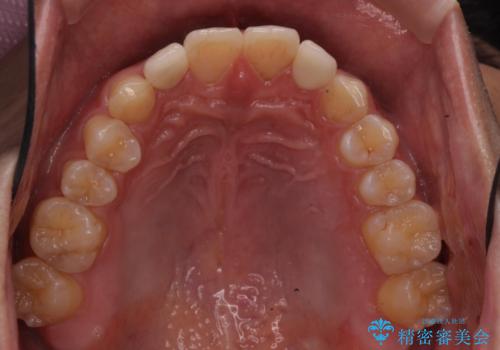

矯正治療で1番目の歯を寄せて2番目の歯はセラミックで形をととのえています。

- 矯正治療費 93.5万円 (セラミック代別)費用は治療当時の料金となります

さらに下の前歯にがたつきがある場合は下の前歯を後ろに下げること自体が難しくなるため、生まれつき歯の形が特殊な場合は、上のすき間を適切な位置にずらして、しかるべき歯にセラミッククラウンを被せて形態修正とスペースを埋めるというのが効率の良い治療方法と言えます。